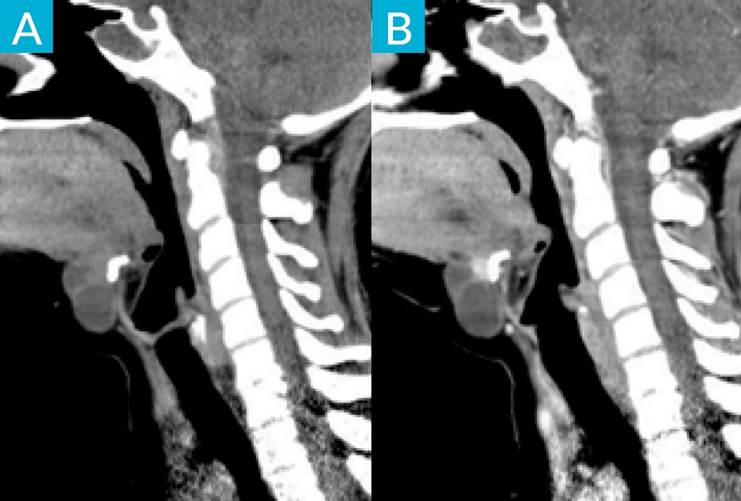

Cervical ultrasound demonstrated a 4 x 3 cm mainly cystic lesion, consistent with a thyroglossal duct cyst (TGDC), presenting focal solid areas with microcalcifications. Contrast-enhanced computed tomography (CE-CT) showed the lesion located in front of the hyoid bone, with upward extension into oral cavity, and revealed an enhancing mural nodule. These characteristics raised suspicion of malignancy, specifically for papillary carcinoma due to the presence of microcalcifications. A fine needle aspiration biopsy (FNAB) was performed, which revealed cancerous cells, consistent with TGDC papillary carcinoma.

Cervical ultrasound and CE-CT are fundamental to characterize and adequately stage these lesions. Carcinoma should be considered in TDGC that have a mural nodule or microcalcifications, which correspond to the psammoma bodies seen histologically in papillary carcinomas.5 FNAB is an important tool to evaluate suspicious lesions but has a low sensitivity.4 The diagnosis of TGDC carcinoma can be confirmed in the post-operative histopathological examination.1

The mainstay of treatment is the Sistrunk procedure, which consists of excision of TGDC, the central portion of hyoid bone and a core of tissue around thyroglossal tract to open into the oral cavity at the foramen cecum. Thyroidectomy and neck dissection should be considered, depending on risk stratification and if there is concurred malignancy.1,4